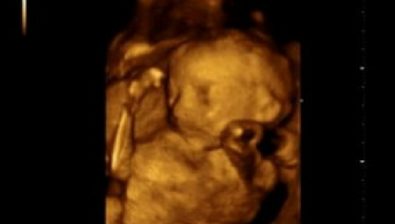

Ultrasound at 25 Weeks

Although you won’t be able to see it, your baby’s blood flow has increased in his/her epidermis and dermis (top layers of skin) so that it reveals a darker shade of pink.

You might see your baby moving, sucking his/her thumb, and even opening and closing his/her mouth to swallow.

These little movements are all just practice for functioning in the big wide world one day soon.